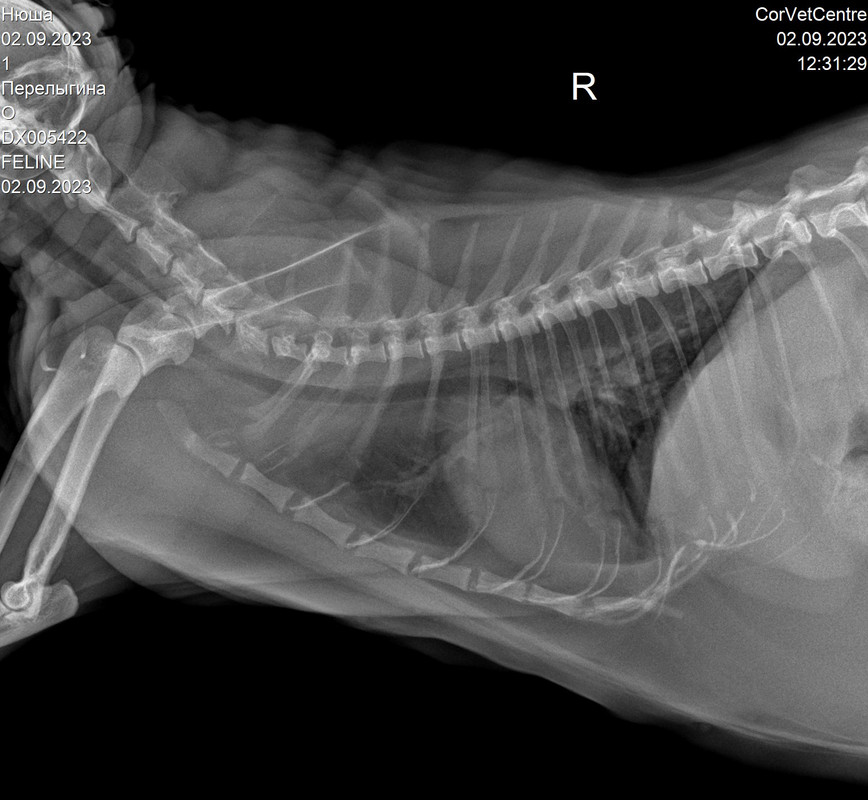

Рентгенологическая диагностика саркомы у кошек

Раздел: Визуальный дайджест